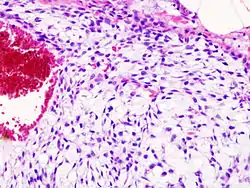

Imaging studies - including radiographs ("x-rays"), computerized tomography (CT), and magnetic resonance imaging (MRI) - are often used to make a presumptive diagnosis of chondrosarcoma.[11] However, a definitive diagnosis depends on the identification of malignant cancer cells producing cartilage in a biopsy specimen that has been examined by a pathologist. In a few cases, usually of highly anaplastic tumors, immunohistochemistry (IHC) is required.

Histopathology